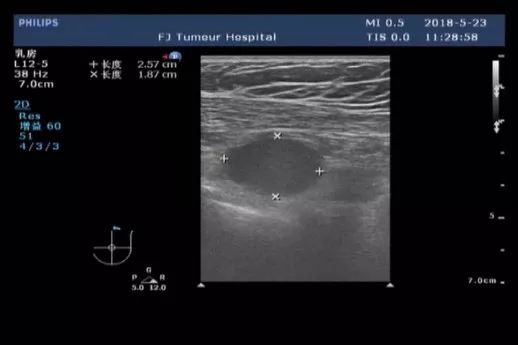

女性患者,30岁,未绝经,家族史不详(患者本人为领养)。于2018-01发现左乳肿块,当地医院乳腺MRI示:左侧乳腺外上象限可见5*7cm大小团块状影,左侧腋下可见多个肿大的淋巴结。B超提示:左乳外上象限探及一低回声区,大小约4.9cm×3.9cm,边缘不规则,可见成角、毛刺,内部回声不均;左腋上中下组探及数个低回声,大者约2.2cm×1.8cm,边界尚清,类圆形,皮髓质分界不清,皮质不规则增厚,淋巴结门消失;右乳及右腋窝未见异常。 PET-CT结果:1、考虑左乳外上象限癌累及胸大、小肌。 2、考虑左锁骨区、左胸大肌及胸小肌深面、左腋窝多发淋巴结转移。

▎疗效评估: B超(2018-04):左乳外上象限探及一低回声区,大小约4.9cm×3.9cm,边缘不规则,可见成角、毛刺,内部回声不均;左腋中下组探及数个低回声,大者约2.5cm×1.6cm,边界尚清,类圆形,皮髓质分界不清,皮质不规则增厚,淋巴结门消失;右乳及右腋窝未见异常。